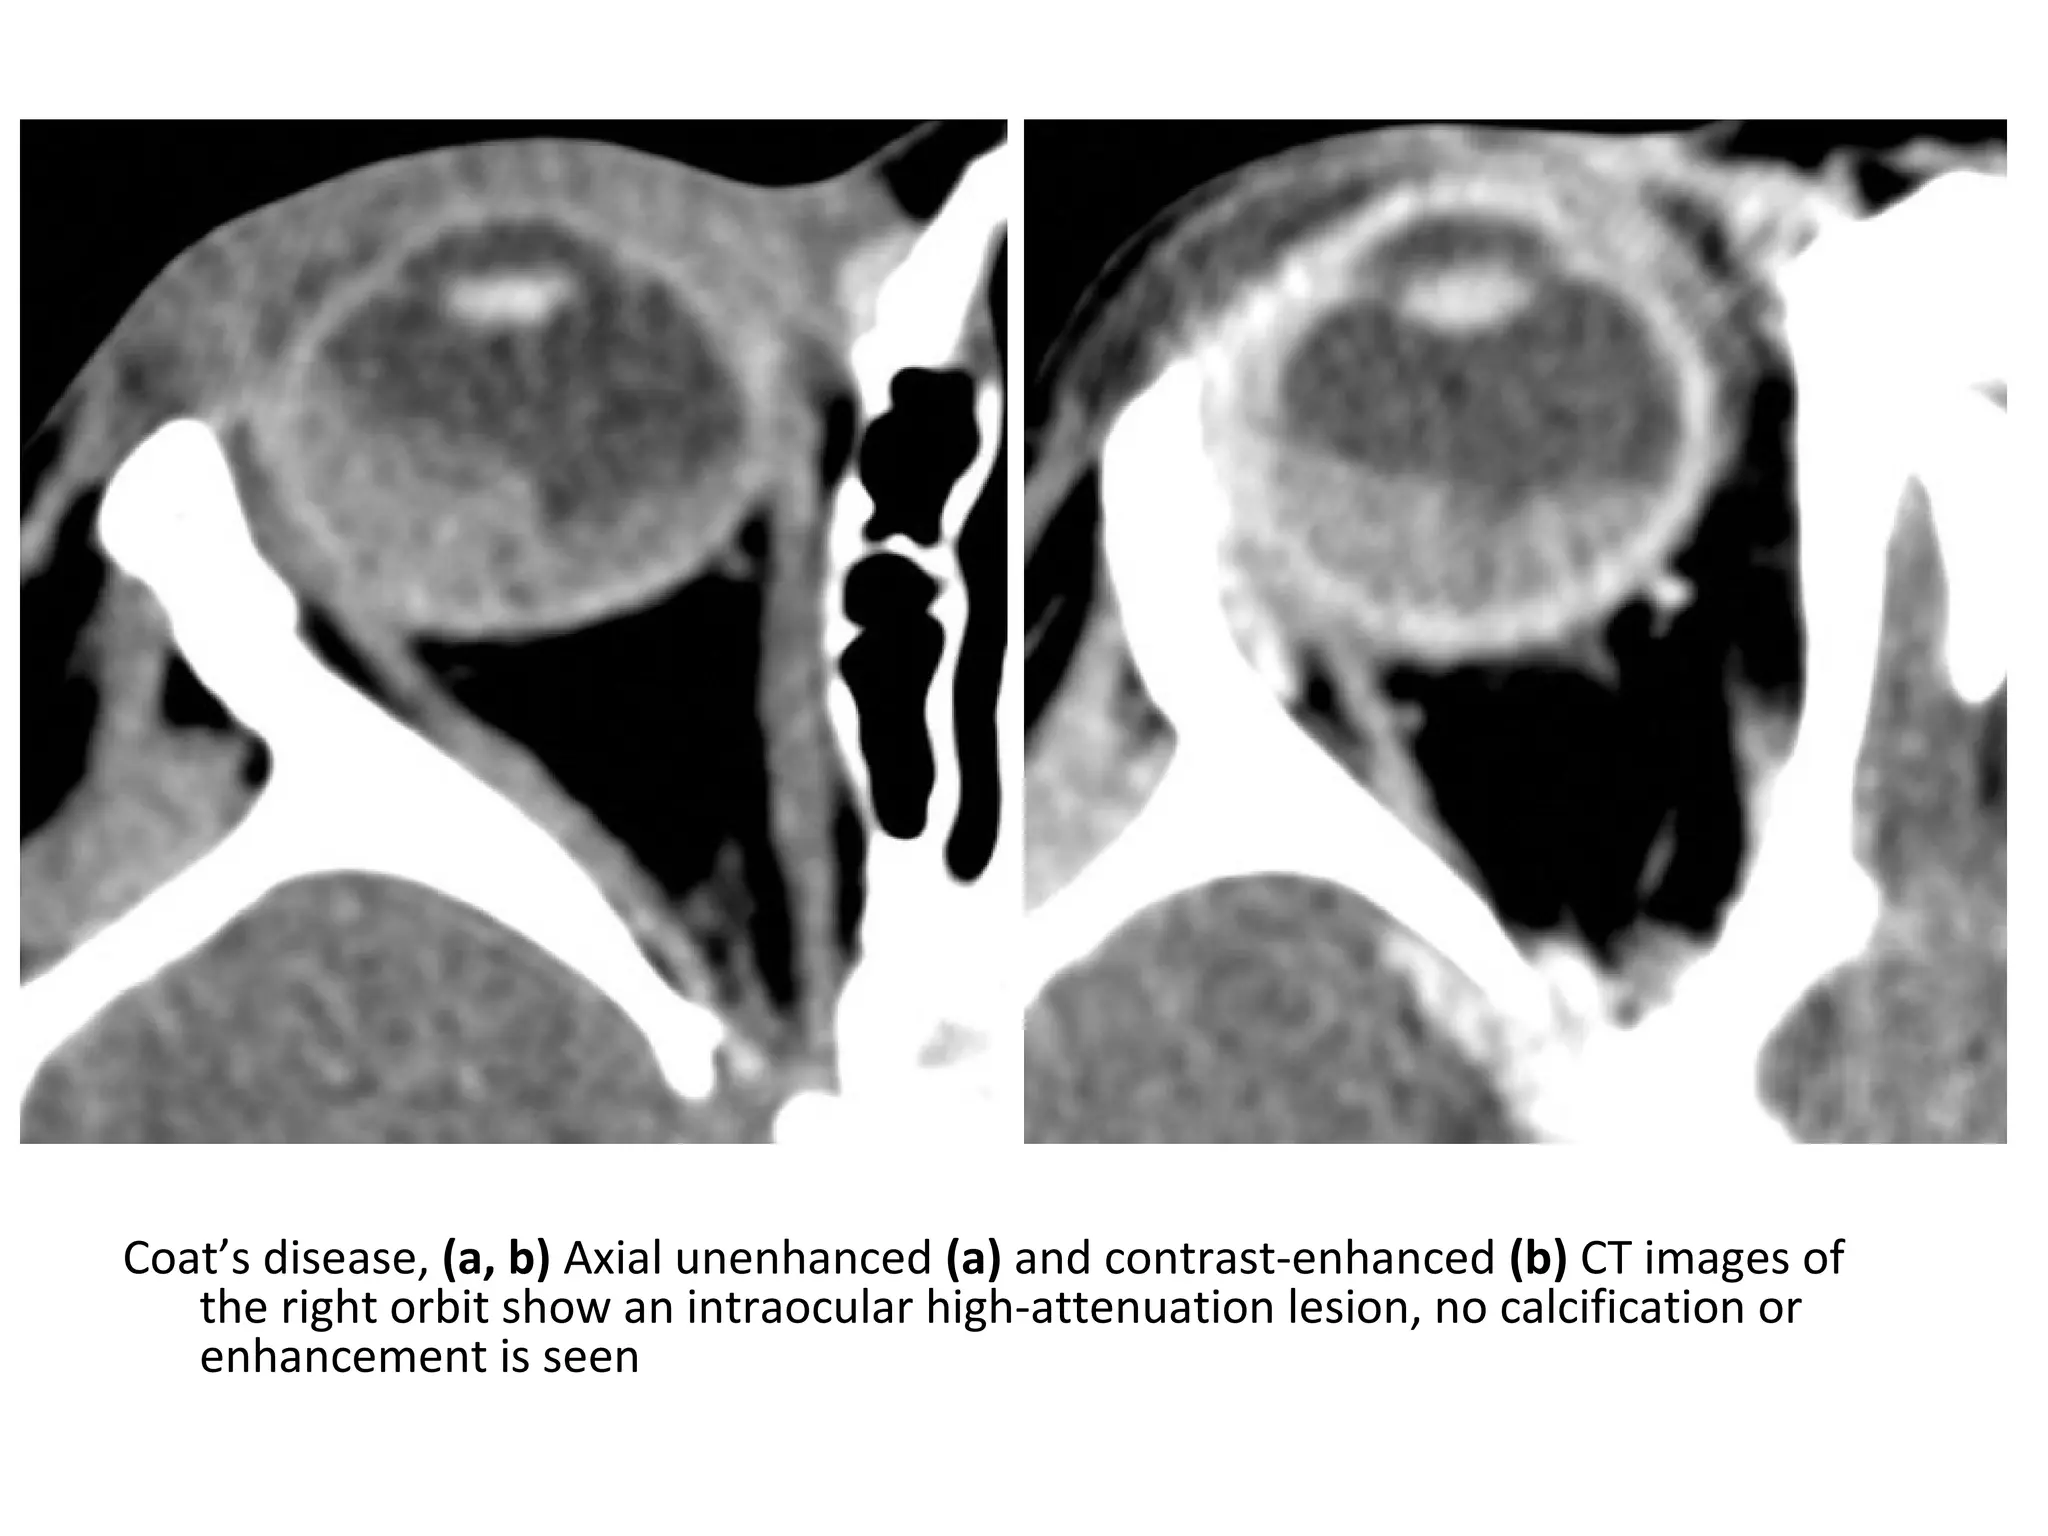

Coat’s disease, (a, b) Axial unenhanced (a) and contrast-enhanced (b) CT images of

the right orbit show an intraocular high-attenuation lesion, no calcification or

enhancement is seen